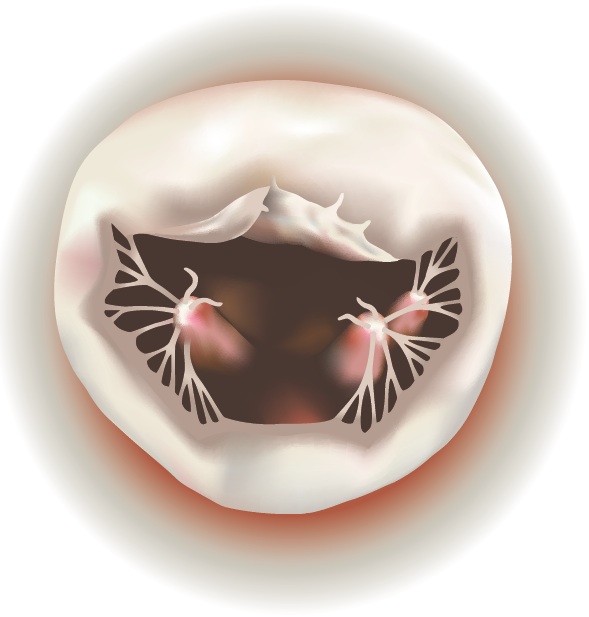

The mitral valve consists of two leaflets, supported by chordae and papillary muscles, and located between the left atrium and left ventricle of the heart. The mitral valve prevents blood from leaking back into the lungs when the heart contracts. When the valve fails, patients may be severely affected.

Degenerative mitral valve disease is a common disorder affecting around 2% of the population. Common findings include a “prolapse” ( slipping or falling our of place), due to elongation or rupture of the chordal apparatus. When the two leaflets fail to close tightly, the mitral valve becomes insufficient, sometimes allowing blood to leak back into the atrium from the ventricle.

A prolapse can occur on either the anterior (front) leaflet or the posterior (rear) leaflet. Usually, the annulus, where the leaflets attach, is also dilated or enlarged.

| Mitral Valve Prolapse on Anterior Leaflet | Mitral Valve Prolapse on Posterior Leaflet |